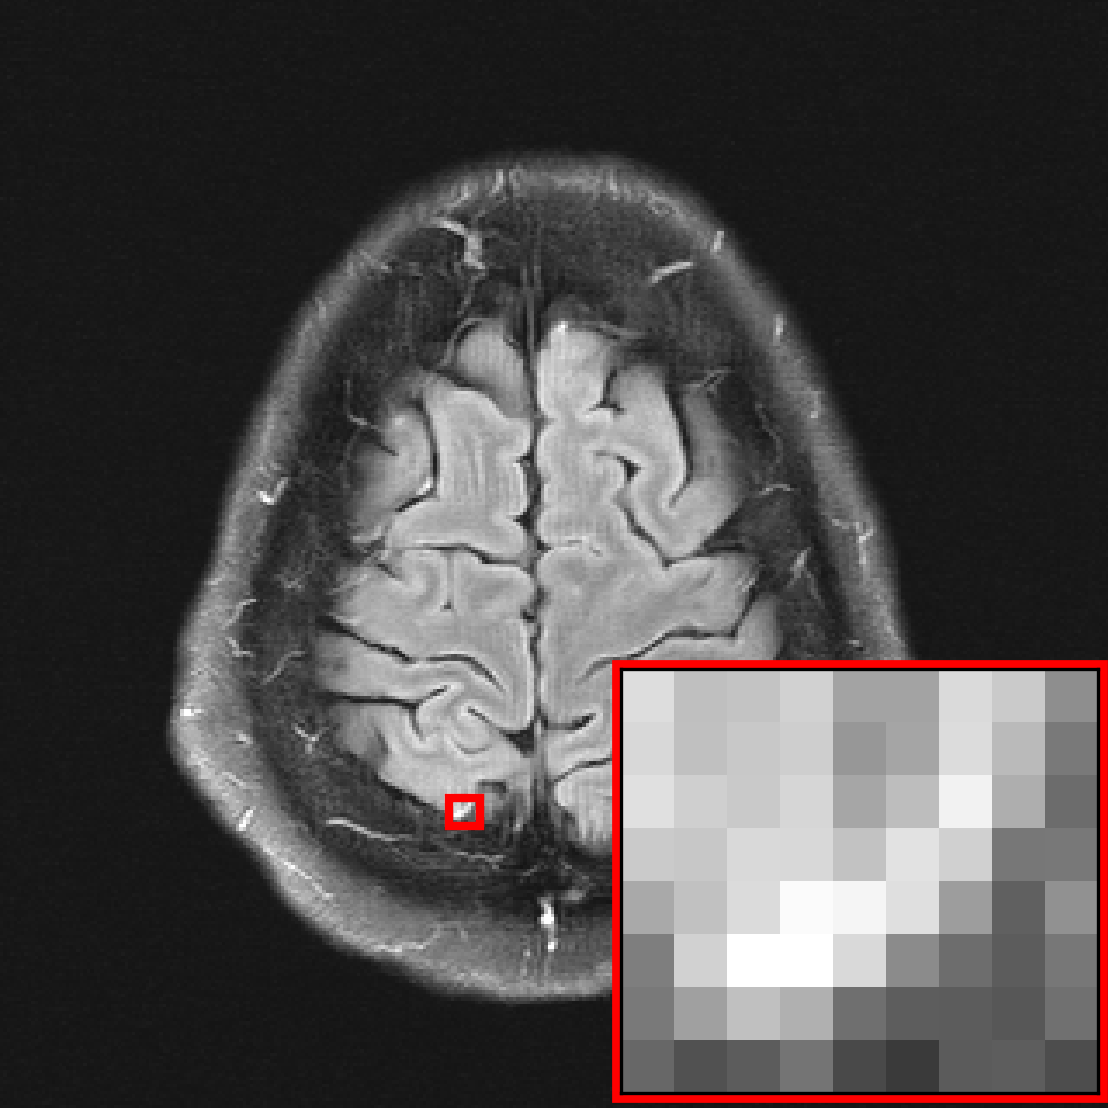

In this section, we investigate the distribution shift from healthy to non-healthy subjects by measuring how well models reconstruct images containing a pathology if no pathologies are contained in the training set. We find that models trained on fastMRI data without pathologies reconstruct fastMRI data with pathologies equally well as the same models trained on fastMRI data with pathologies.

Figure 5 shows the performance of each model evaluated on as a function of its performance evaluated on . Reconstructions are evaluated only on the region containing the pathology, where we further distinguish between small pathologies that take up less than of the total image size and large pathologies that take up more than of the total image size.

We see that the models trained on show essentially the same performance (SSIM) as models trained on regardless of pathology size. The results indicate that models trained on images without pathologies can reconstruct pathologies as accurately as models trained on images with pathologies. This is further illustrated in Figure 6 (and Figure 16), where we show reconstructions given by the VarNet of images with a pathology: the model recovers the pathology well even though no pathologies are in the training set. Figure 14 in the appendix provides a more nuanced evaluation of the SSIM values for VarNet.